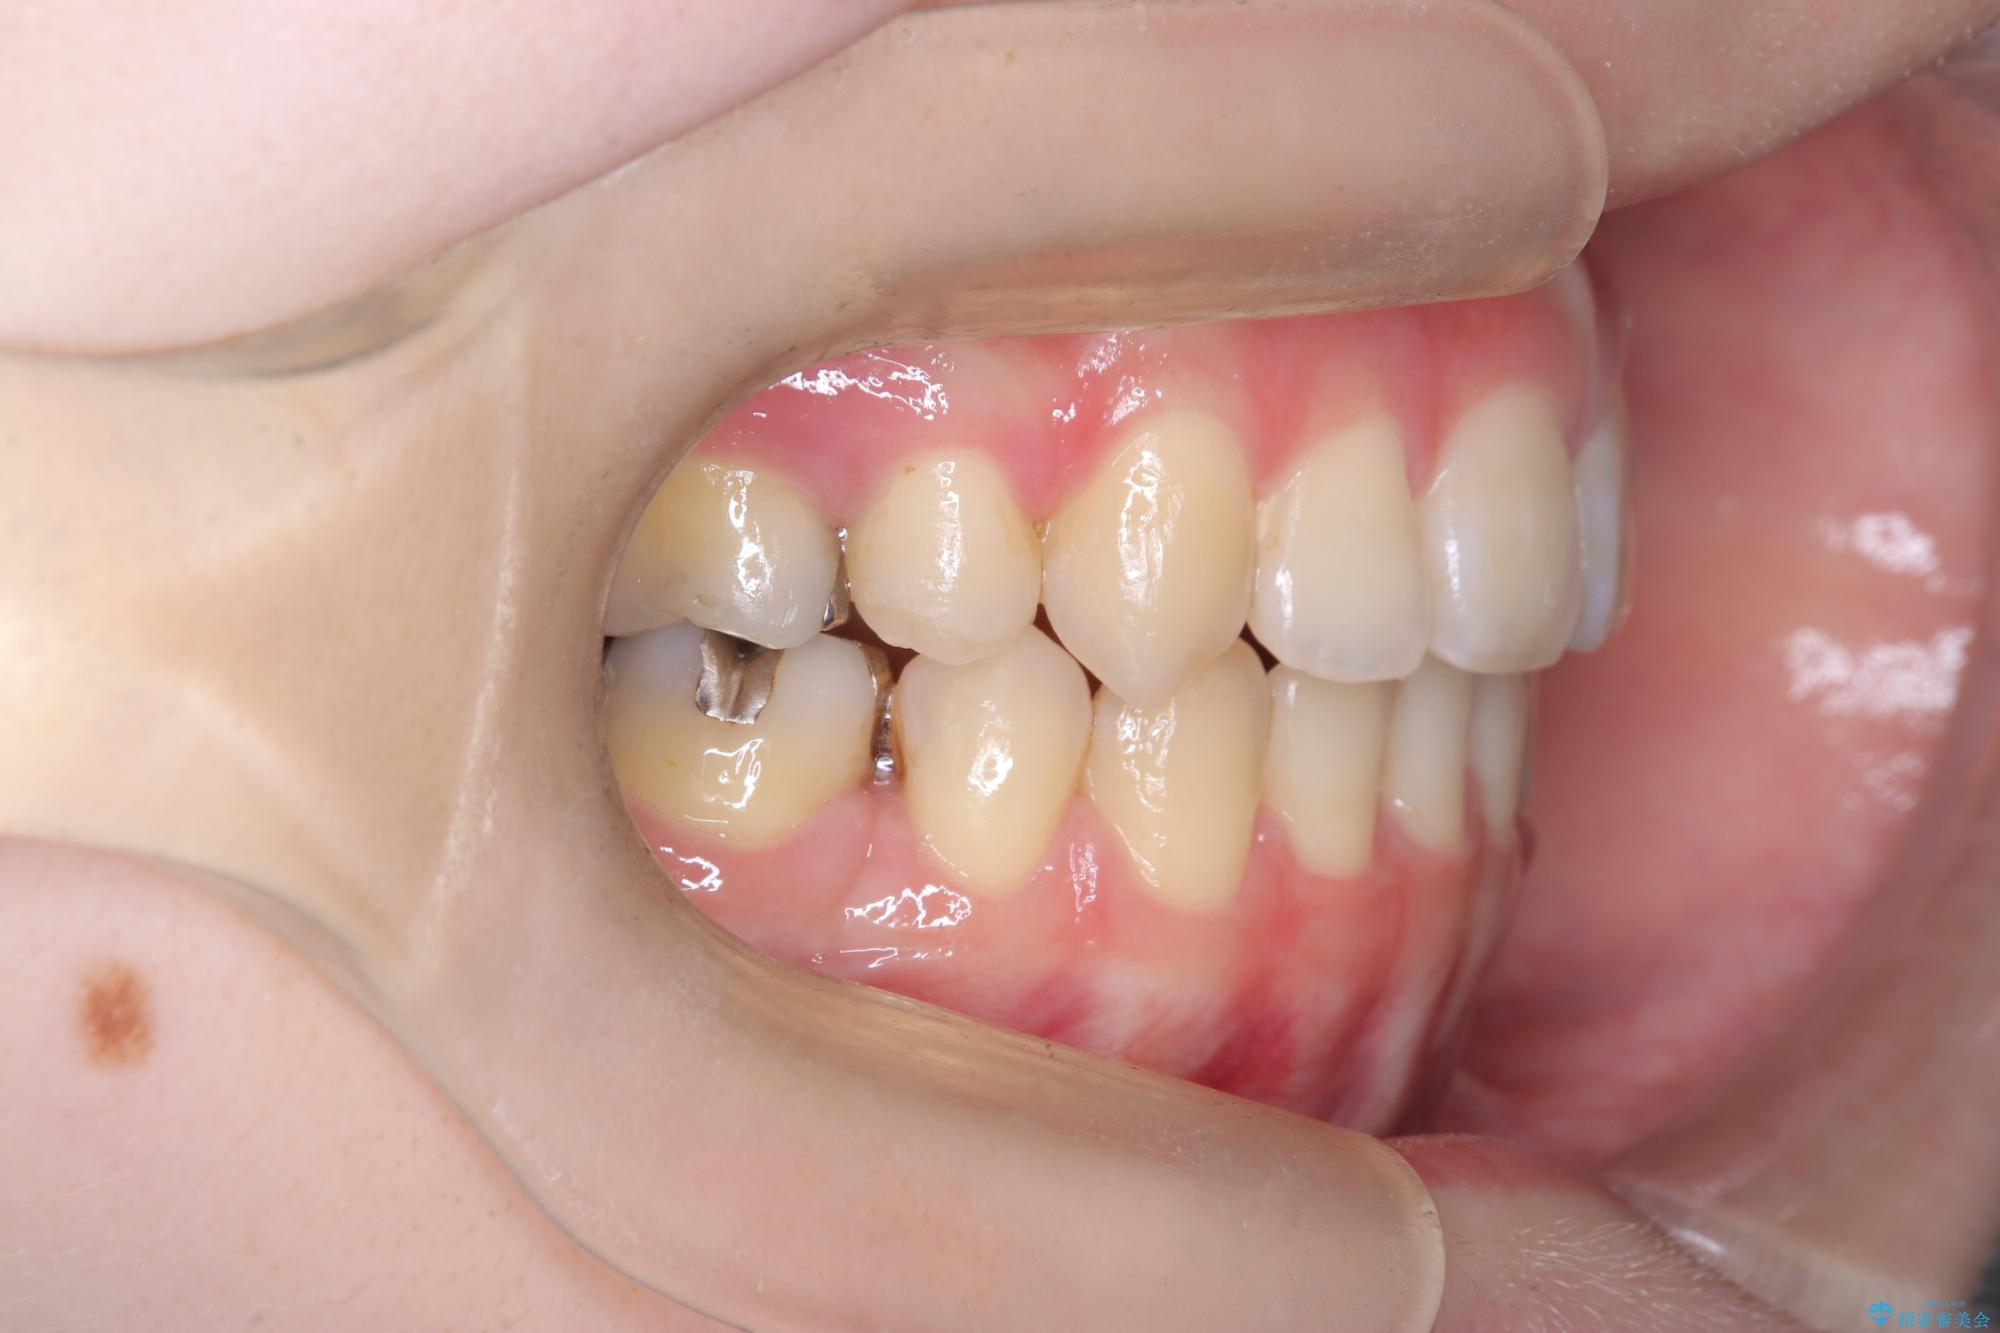

- 開咬と歯のデコボコ(叢生)、八重歯を主訴にご来院された患者様です。

矯正の精密検査の結果、上顎左右4番および下顎左右5番の計4本を抜歯し、ワイヤー矯正(クリア装置)にて治療を行いました。

虫歯があったので、虫歯治療は矯正前に行っています。